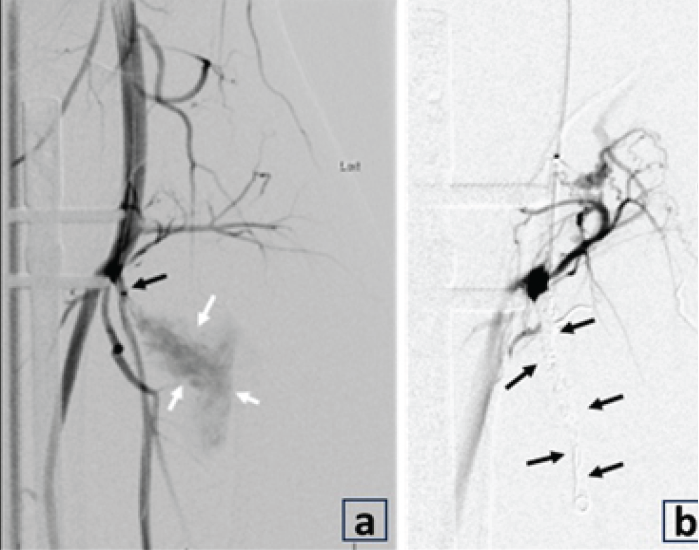

Figure 1: (a) Pre-operative radiograph reveals acute, mildly comminuted fractures of the mid/distal tibia and proximal fibular shaft. (b) Post-operative radiograph reveals intramedullary nailing of tibial shaft fracture in improved alignment and proximal fibular shaft fracture with increased displacement and apex posterior angulation. Upon the present presentation with the increased lateral calf pain and swelling, Doppler ultrasound revealed a large pseudoaneurysm of the ATA with the characteristic yin-yang sign (Fig. 2). CTA confirmed a pseudoaneurysm arising from the proximal ATA, surrounded by a large hematoma in the leg (Fig. 3). The largest aneurysmal sac measured approximately 8.7 × 10.4 × 16.1 cm, with an actively filling, non-thrombosed component measuring about 3.4 × 3.8 × 6.5 cm. Given the significant compressive symptoms caused by the hematoma, coil embolization of the ATA was performed to exclude blood flow into the pseudoaneurysm cavity. Selective catheterization of the left ATA was achieved through ultrasound-guided puncture of the right common femoral artery. Multiple Penumbra Ruby coils were deployed into the proximal and distal segments of the ATA, effectively sealing the pseudoaneurysm defect. A pre- and post-procedural angiogram demonstrated successful cessation of blood flow into the pseudoaneurysm cavity (Fig. 4a and b).

Figure 4: (a and b) Angiogram after selective catheterization of the left anterior tibial artery (ATA) demonstrates contrast filling of pseudoaneurysm (white arrows) and the origin at the proximal ATA (black arrow) near the screw. After coil embolization (b), the angiogram shows no contrast filling into the pseudoaneurysm cavity (black arrows), consistent with the successful cessation of blood flow into the pseudoaneurysm cavity. Following embolization, a left leg incision was made over the most prominent area of fluctuance, and the large hematoma cavity was entered. Suction and manual evacuation were used to remove approximately 250 cc of old thrombus along with the pseudoaneurysm capsule. A closed suction drain was placed in the evacuated cavity, and the incision was closed with interrupted nylon sutures. Sterile dressings were applied. The post-operative course was uncomplicated, and the patient recovered well. At the 3-month follow-up, CTA demonstrated post-procedural changes consistent with embolization of the ATA pseudoaneurysm. The distal ATA remained patent, with no evidence of recurrence. The aneurysm neck was successfully sealed, and there was a reduction in the size of the aneurysm sac (Fig. 5).